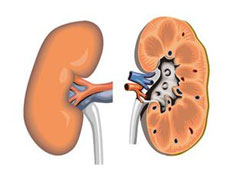

急性肾衰竭(ARF)

疾病介绍:急性肾衰竭(ARF)是指肾小球滤过功能在数小时至数周内迅速降低而引起的以水、电解质和酸碱平衡失调以及氮质代谢产物蓄积为主要特征的一组临床综合症,…【详细】